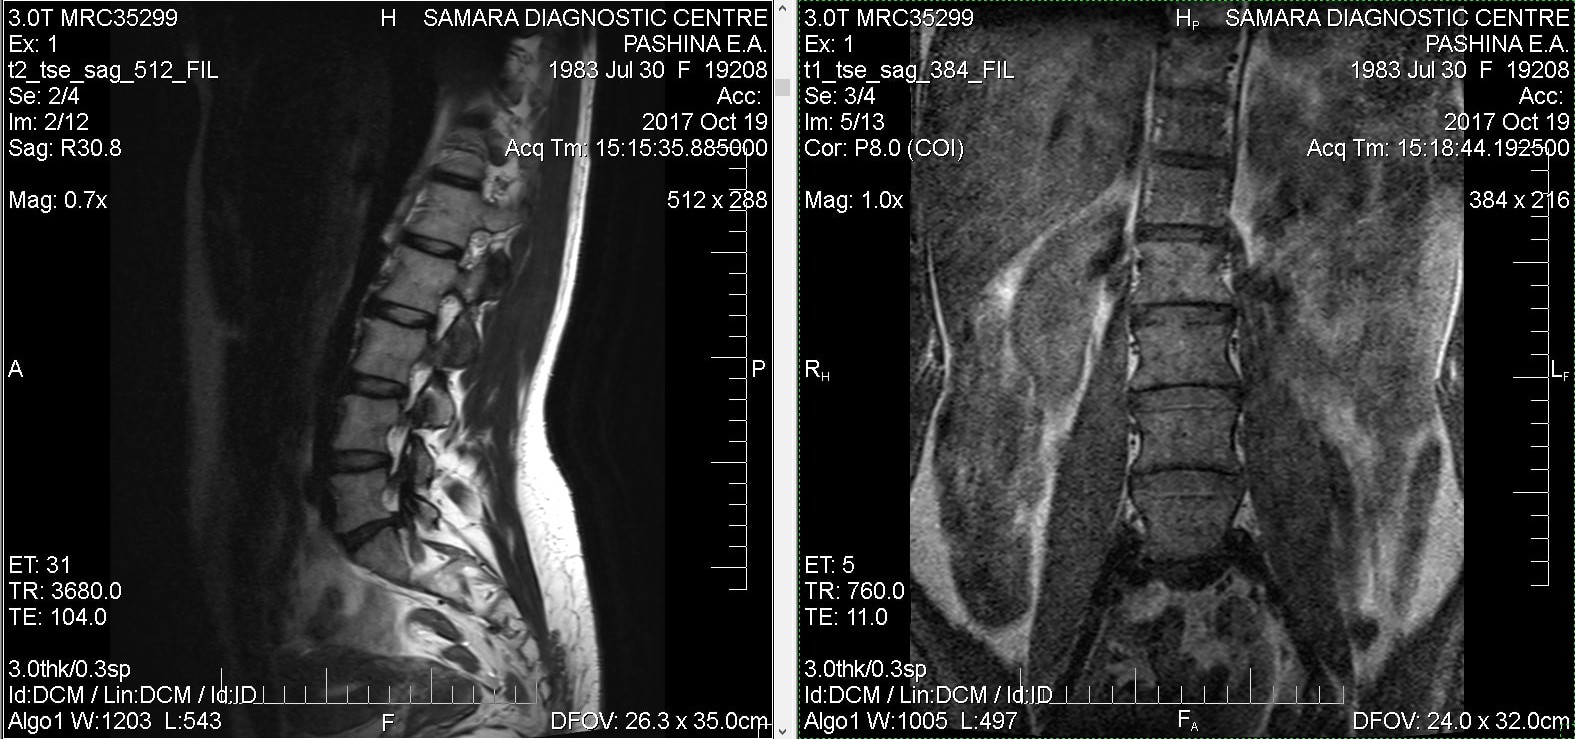

Тренировки с межпозвоночной грыжей.